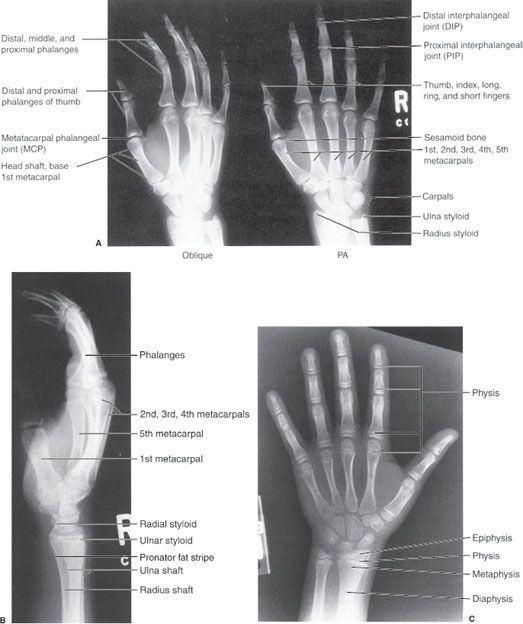

x ray of right hand and wrist